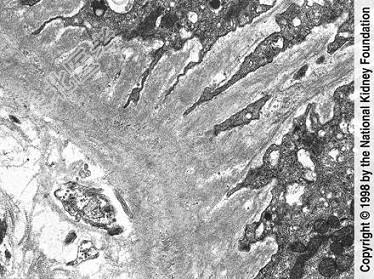

- 单项选择题如图,银染色可见系膜区及毛细血管袢有淀粉样物质沉积, 刚果红染色呈砖红色阳性,电镜以淀粉样纤维沉积为特点, 其病理诊断可考虑为 ( )